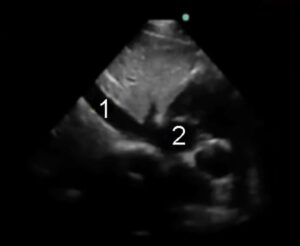

Sottocostale 4 camere (S4C)

Posizione della sonda

Si trova generalmente un paio di centimetri sotto al processo xifoideo dello sterno. Per ottenere le immagini migliori ci si avvale del fegato per la sua ecogenicità, piuttosto che dello stomaco; la sonda, quindi, va mantenuta a livello mediano se non leggermente alla destra del paziente, con l’indicatore della sonda rivolto alla sinistra del paziente. Applicare pressione per affondare la sonda al di sotto del livello dello sterno può migliorare la visione.

- Parenchima epatico

- Ventricolo destro

- Ventricolo sinistro

- Atrio destro

- Atrio sinistro

Da questa finestra appare una sezione più bassa del ventricolo destro rispetto all’apicale quattro camere, con una visione del ventricolo sinistro meno informativa rispetto alle finestre precedentemente elencate

Da questa finestra è ben visibile la parete libera del ventricolo destro, complementando così le informazioni ottenute dalle altre finestre. È comunque possibile una valutazione globale anche da questa finestra, nel caso in cui le altre finestre siano scarsamente accessibili.

Il ventricolo destro deve normalmente avere dimensioni inferiori rispetto al sinistro. Da questa finestra le dimensioni del ventricolo destro sono tuttavia generalmente sottostimate.

Questa finestra è anche ottimale per la valutazione del versamento pericardico, osservabile quando il cuore è circondato da uno spazio anecogeno. Il tamponamento cardiaco può manifestarsi con inversione dell’atrio destro durante la sistole, compressione del ventricolo destro durante la diastole e dilatazione della vena cava inferiore. Inoltre è una finestra che può essere utilizzata per valutare la qualità delle compressioni toraciche in corso di rianimazione cardiopolmonare.

Sottocostale vena cava inferiore

Partendo dalla visione sottocostale quattro camere, centrando l’atrio e ruotando la sonda fino a puntare il marker verso la testa del paziente si dovrebbe ottenere l’immagine della VCI che si abbocca nell’atrio destro.

- Vena cava inferiore

Nella parte superiore dell’immagine si osserva il parenchima epatico, sovrastante alla VCI visibile in orizzontale mentre entra nell’atrio di destra. La vena epatica che si immette nella VCI è frequentemente visibile a breve distanza dall’atrio destro, sopra alla VCI. È importante fare attenzione a non confondere la VCI con l’aorta, che solitamente ha una parete più spessa e una chiara attività pulsatile.

La valutazione delle dimensioni della VCI è generalmente usata come indice di stato volemico e predittore di fluid responsiveness21. Una VCI dilatata è suggestiva di elevate pressioni venose centrali e indica minori probabilità di fluid responsiveness. Una VCI piccola e collabente è spesso osservabile in pazienti in condizioni di fluid responsiveness. Si tenga in mente che la valutazione dello stato volemico è un aspetto molto complesso, le informazioni raccolte mediante ecografia devono essere integrate nel contesto clinico e non prese da sole.